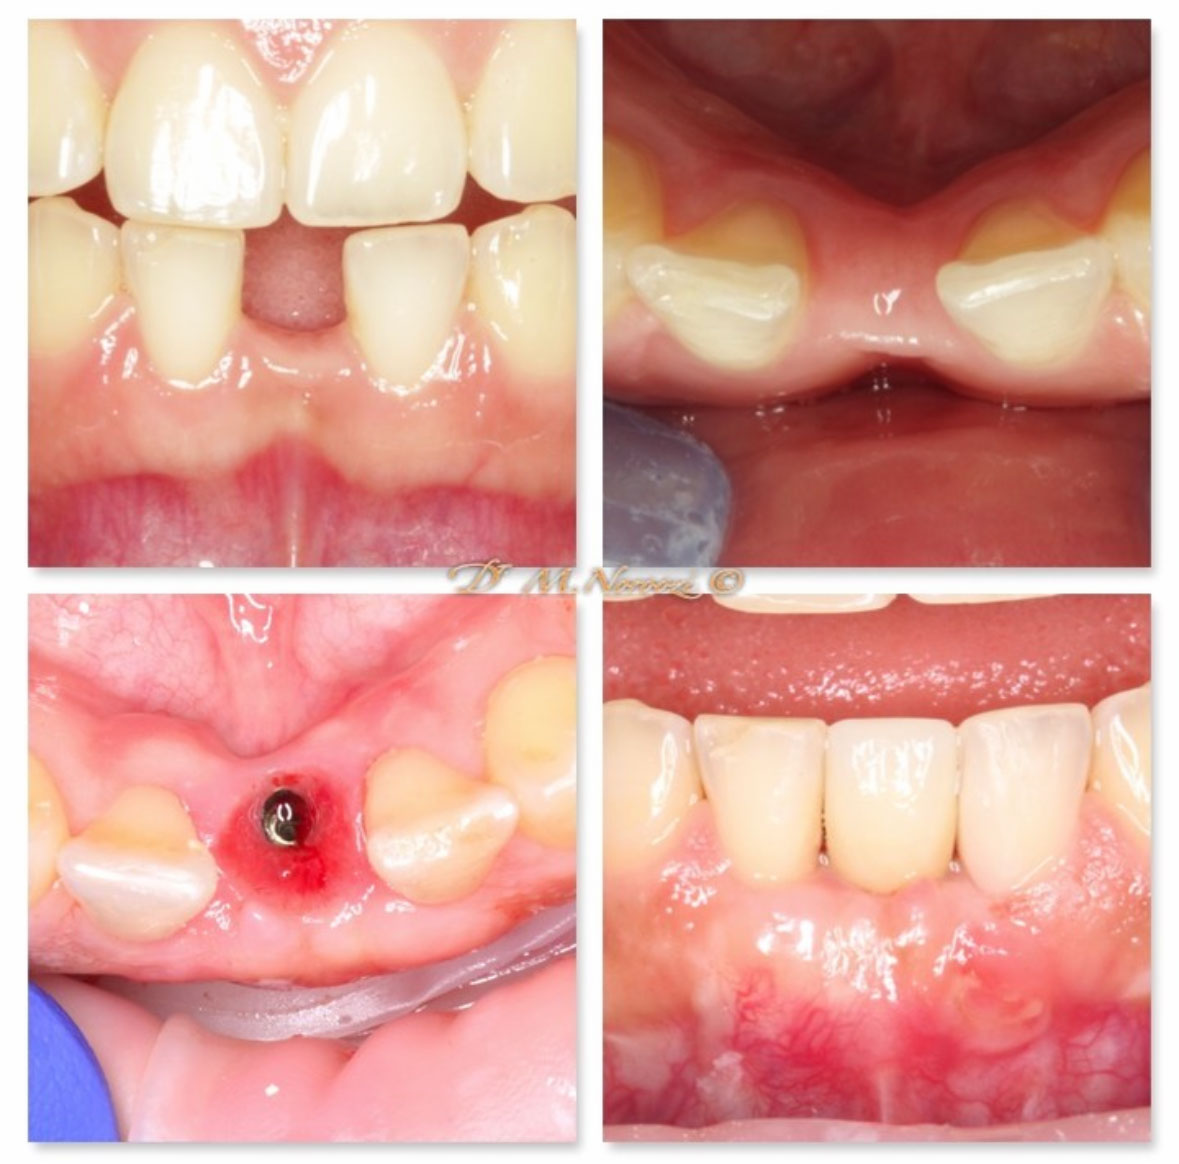

Before & Afters of Dental Implant Patients

Complete Dental Implant Cases Gallery

Surgical advances with SAME-DAY IMPLANTS in Vancouver BC

Using the most recent advances in dental implant technology, Dr. Noroozi is able to place single stage implants. These implants do not require a second procedure to uncover them but may require a minimum of six weeks of healing time before artificial teeth are placed. There are even situations where the implant can be placed at the same time as the tooth extraction and the artificial tooth can be inserted immediately following the implant placement – further minimizing your number of surgical procedures.

General Disclaimer: The results in the photographs are examples only and do not imply any certainty of the result of a procedure, and all outcomes are subject to the circumstances of the individual patient.